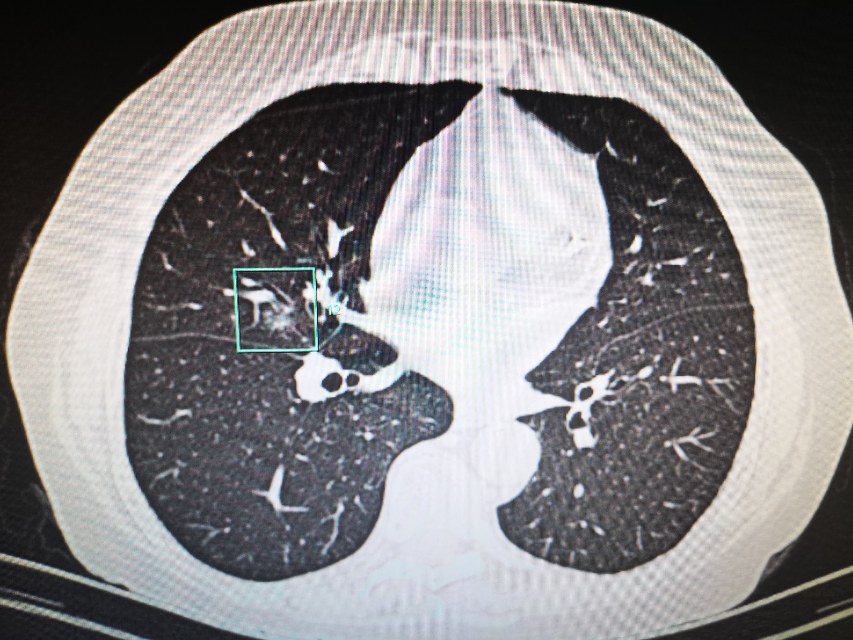

接过CT片,李医生仔细分析起来。果然又是一例顽皮的肺磨玻璃。只见,在右肺中叶外侧段,一个8mm的混合磨玻璃结节,躲藏在封闭的房间内,也就是我们常常说的密室。密室的外墙是右肺中叶肺动脉、中叶支气管、斜裂胸膜,门是中叶分支动脉。通往密室的是斜裂和右肺中叶动脉和支气管形成的一个小通道。好在还有路径可以通过!老话说谨言慎行,一点没错😂,不过谁让咱是江湖兵器排行前十的小李飞针呢,为了最小的创伤解决患友的疾苦,咱们必须不畏艰难,知难而进,迎难而上!将密室中的磨玻璃结节消灭!